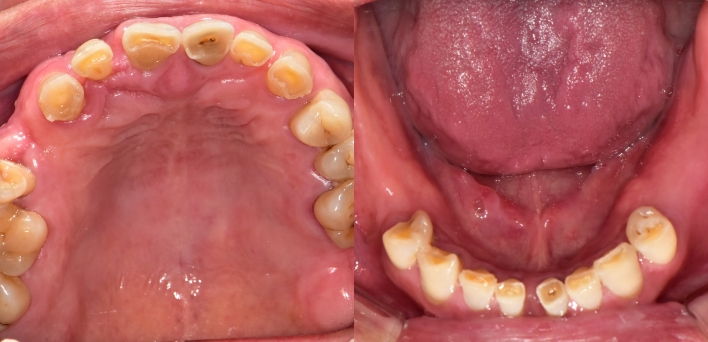

임플란트 : 손 ** 님 (50대)

치아가 있다는게, 아직도 정말 꿈만 같아요.

환자 특징

환자 특징01무치악 상태

환자 특징02수년간 무치악으로 지내심

임플란트가 불가능할것이라

생각하고 내원

위, 아래 6개씩 식립

디지털 풀아치 임플란트